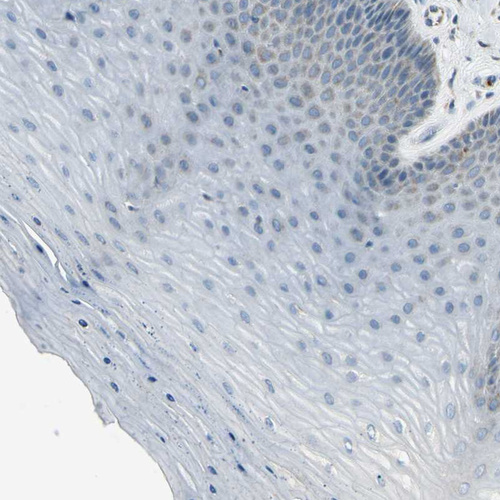

Immunohistochemistry analysis in human lymph node and cervix, uterine tissues using HPA009076 antibody. Corresponding FAM49B RNA-seq data are presented for the same tissues.